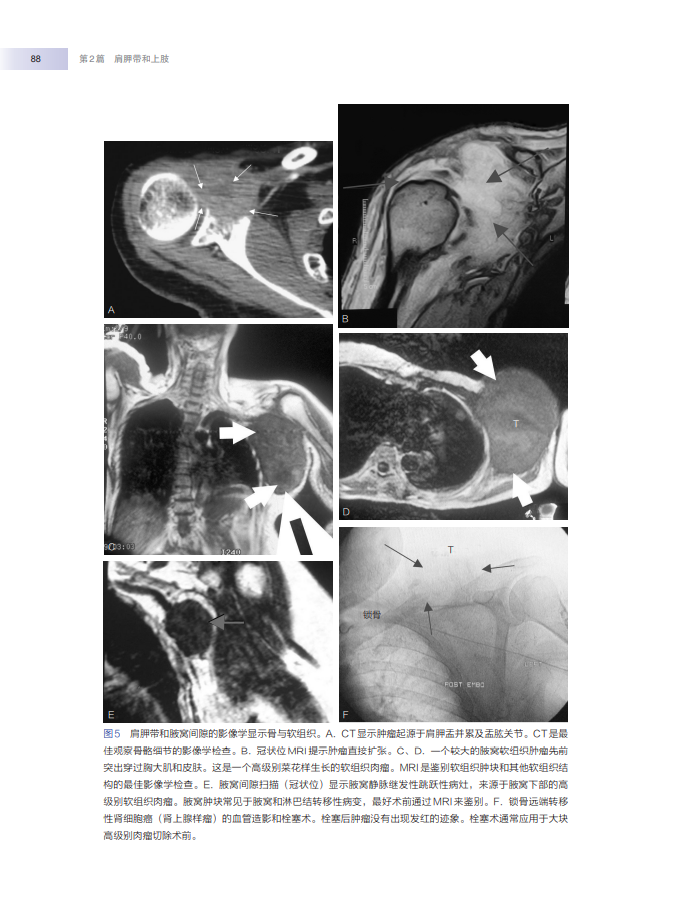

骨肿瘤外科·论述了所有肢体、骨盆和肩胛带肿瘤,以及腹部和躯干部位骨与软组织肿瘤的流行病学、临床症状、影像学特征、病理学、治疗方案、手术方法和注意事项等。